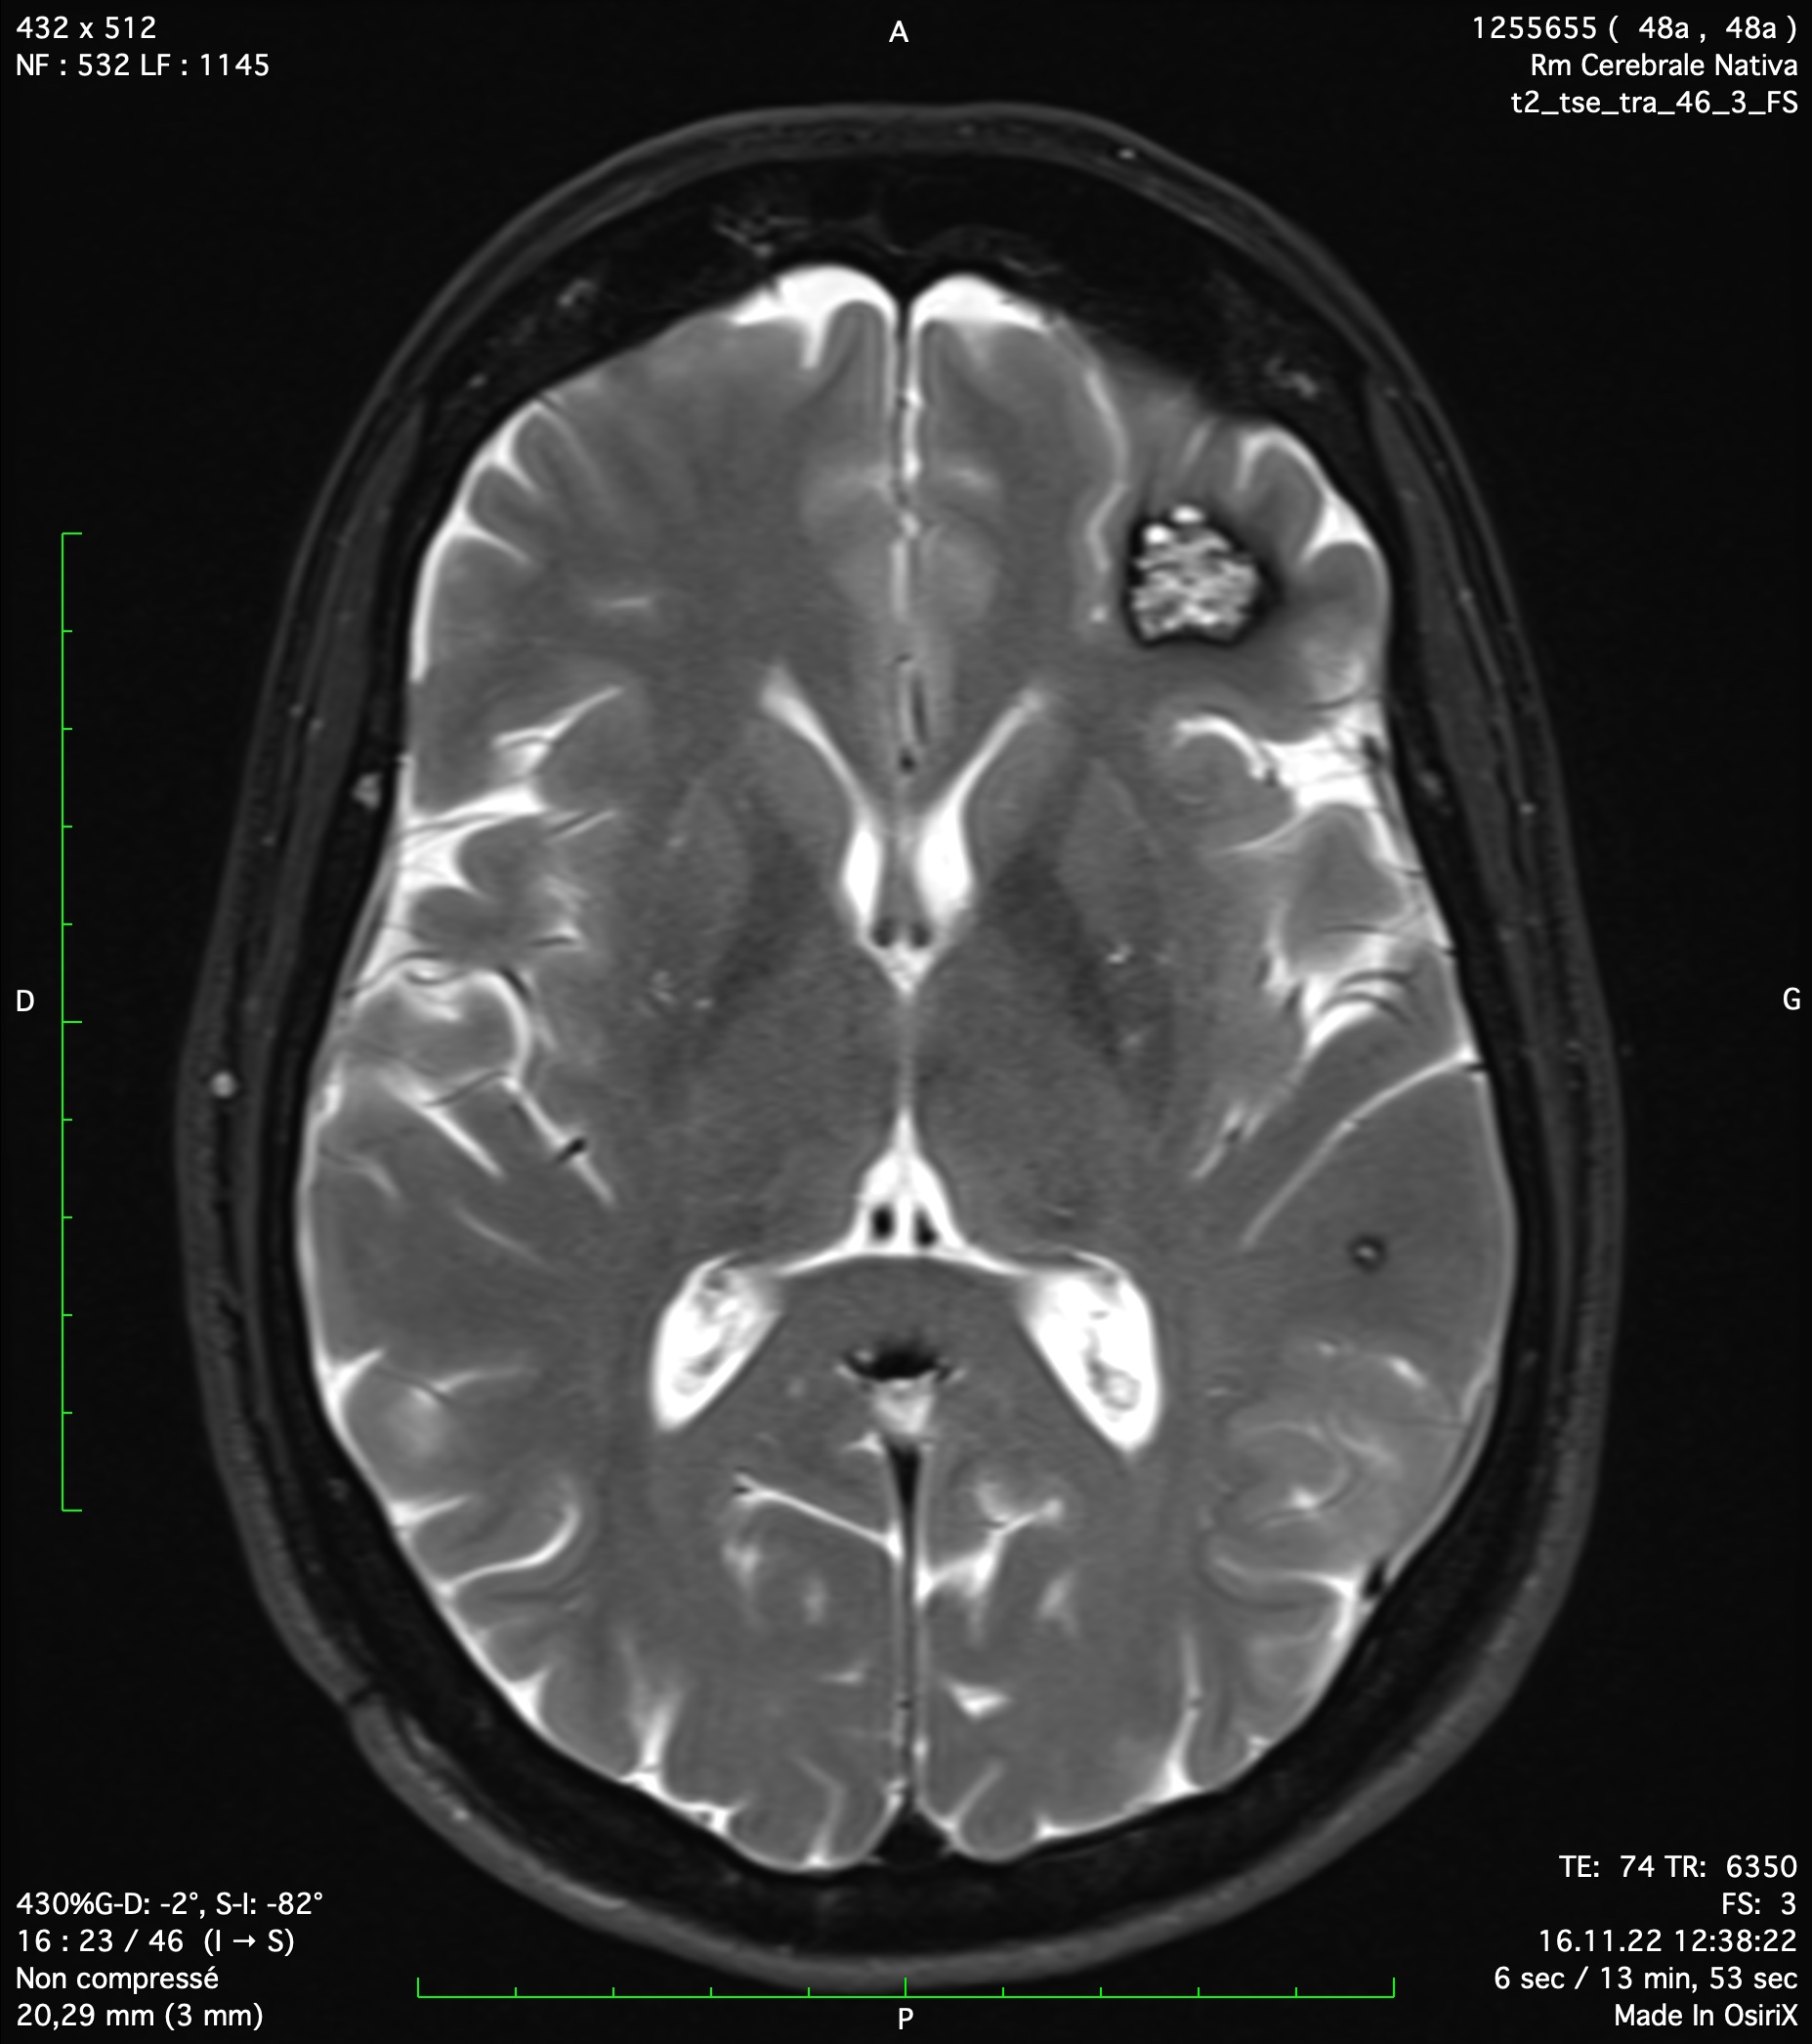

Multiple aneurysms on cerebral arteries

Cerebral aneurysm is due to the arterial wall degeneration. There is a slow process favoriting by common cardio-vascular risk factors (smoking, high blood pressure, cholesterol, diabetes). Genetic factors also play a role in the formation of cerebral aneurysms. A cerebral aneurysm is rarely responsible for a neurologic deficit without bleeding. In rare cases of giant aneurysm, it could present a mass effect on cranial nerve for example.

It is frequent to occasionally discover a cerebral aneurysm, so a neurosurgical consultation is mandatory in such situation. Depending on case-by-case criteria, the risk for bleeding of the aneurysm is evaluated and consequently, the indication or not to treat such aneurysm. Risk factors that increased the risk of bleeding are the aneurysmal sac diameter > 7mm, the localization in posterior circulation, smoking, high blood pressure, familial history.